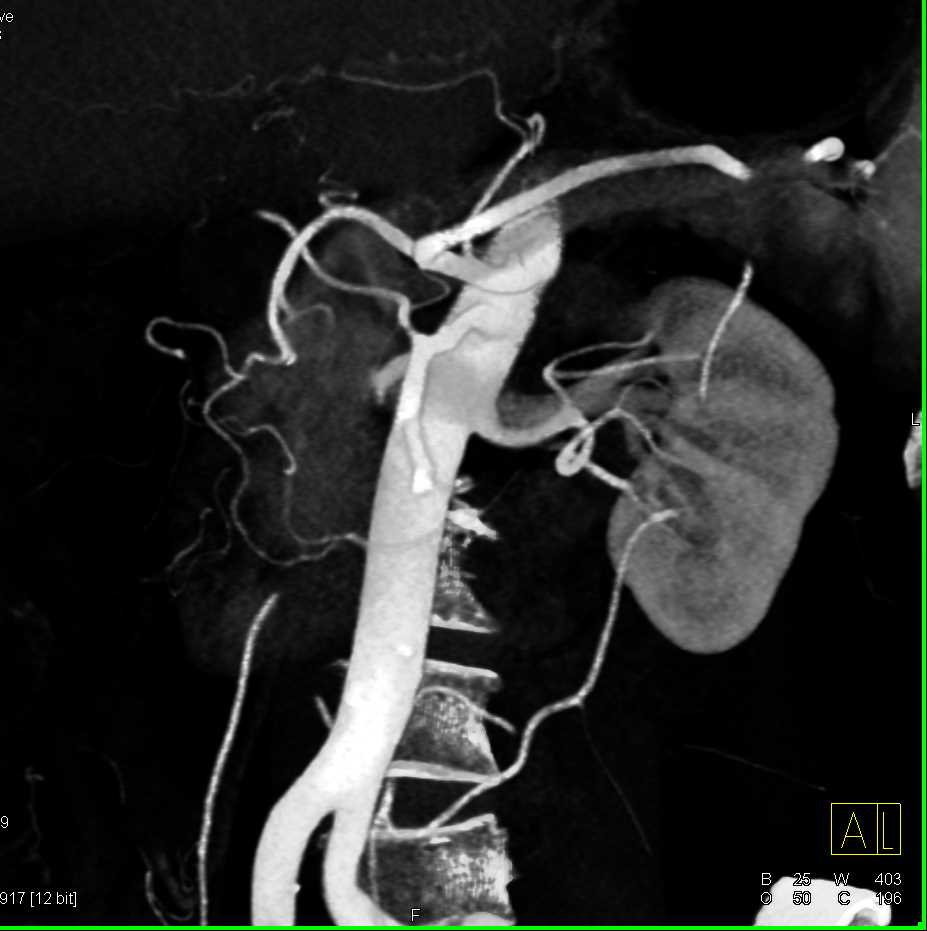

Neuroendocrine Tumor Body of Pancreas